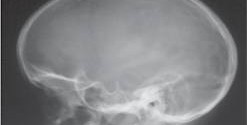

ACROCEFALOSINDACTILIA

La Acrocefalosindactilia es una enfermedad genética hereditaria muy rara, caracterizada por craneosinostosis (cierre prematuro de las suturas), exoftalmos (protrusión anormal del globo del ojo grave), pulgares y dedos anchos y cortos, sindactilia (fusión congénita o accidental de dos o más dedos entre sí), turribraquicefalia (cabeza con vértice puntiagudo), asimetría craneofacial, hipoplasia (desarrollo incompleto o defectuoso) maxilar, hipertelorismo (aumento de la …